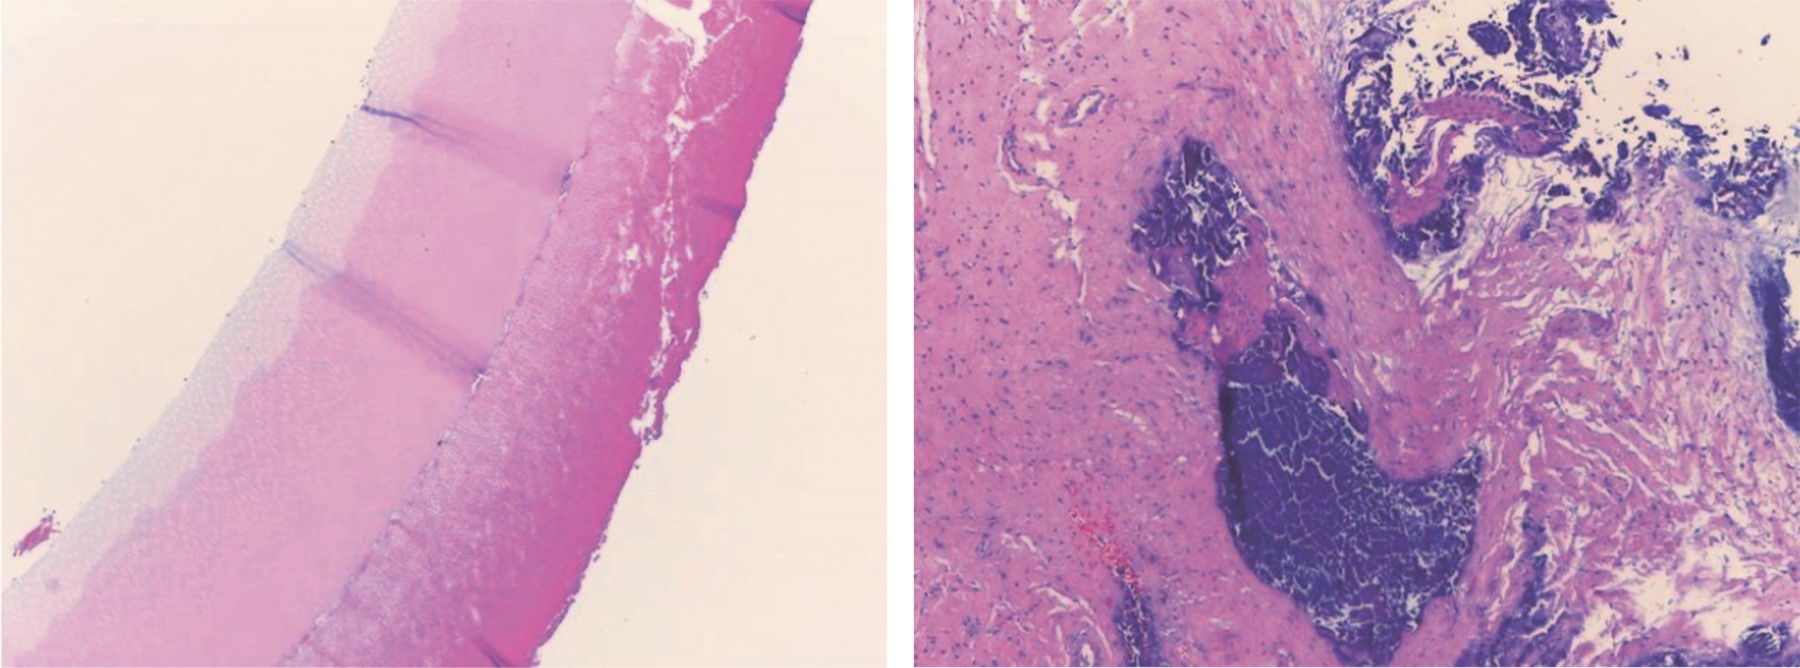

Supernumerary teeth are additional dental organs that exceed the normal number. They can present as single or multiple, unilateral or bilateral, and sometimes may be located anywhere in the dental arch, with a mandibular preference. They have the potential to cause problems with the eruption and alignment of normal dentition, which is why their treatment has often been a subject of debate. This case report describes the surgical approach of a 17-year-old male patient with dental germs present in the lower arch, located bilaterally between the premolars. The treatment plan consists of the extraction of the supernumerary tooth in quadrant 3, using various digital tools to design a surgical guide. The objective of this case is to present a surgical protocol for the extraction of a supernumerary tooth using a digital workflow.

Figure 2